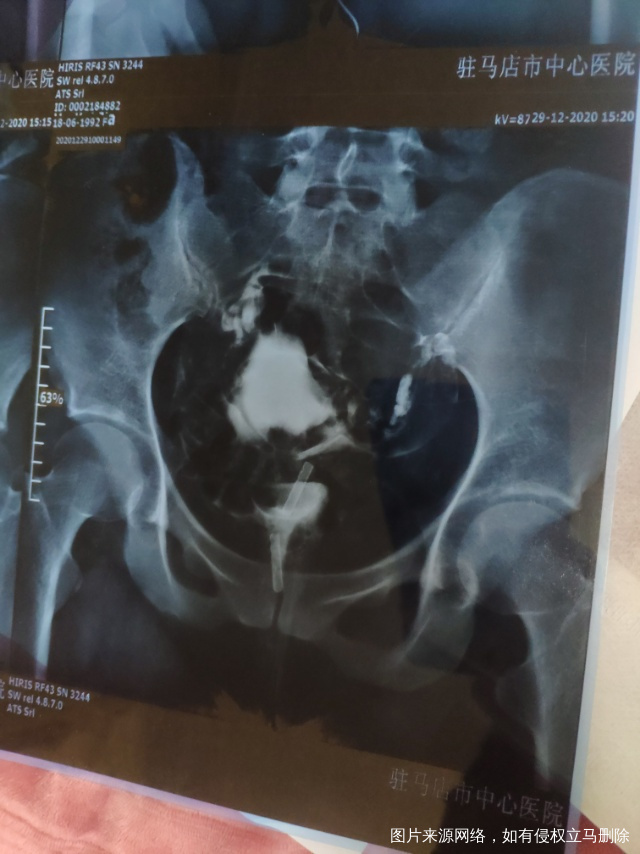

输卵管造影最近做的输卵管造影和之前做的腹腔镜

做完输卵管造影第六天了小腹还是感觉沉甸甸的如